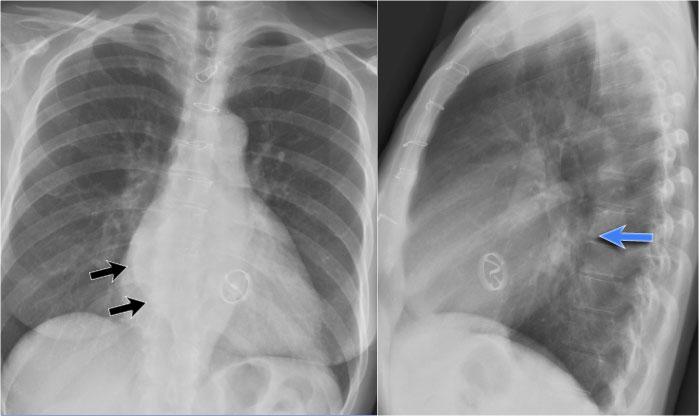

Ví dụ Lâm sàng: Dấu hiệu Kín đáo của Suy tim Sung huyết

Hãy bắt đầu bằng cách xem xét các phim X-quang ngực hiện tại.

Chỉ dựa trên các hình ảnh này, người đọc có thể nghi ngờ suy tim sung huyết (CHF), mặc dù các dấu hiệu còn khá kín đáo.

Bây giờ hãy xem lại phim cũ trước đó…

Việc cuộn qua lại giữa phim hiện tại và phim cũ giúp tăng đáng kể độ tin cậy trong chẩn đoán suy tim sung huyết.

Các dấu hiệu so sánh chính bao gồm:

- Kích thước tim: Tăng nhẹ so với phim trước; tuy nhiên, tim to đã hiện diện từ trước.

- Hệ mạch máu phổi: Cương tụ mạch máu nhẹ gợi ý tăng áp lực tĩnh mạch phổi.

- Hình ảnh mô kẽ: Dấu hiệu kín đáo của phù mô kẽ.

- Tràn dịch màng phổi: Tràn dịch lượng ít hai bên, với thay đổi kín đáo ở bờ dưới-sau của các thùy dưới, gợi ý tích tụ dịch.

Dấu hiệu Silhouette

Dấu hiệu silhouette đề cập đến sự mất đường bờ bình thường giữa các cấu trúc có tỷ trọng X-quang khác nhau, thường gặp nhất là phổi chứa khí tiếp giáp với các cấu trúc phần mềm như tim hoặc cơ hoành.

Dấu hiệu này có vai trò quan trọng trong việc phát hiện các tổn thương kín đáo và định khu tổn thương trong lồng ngực.

Minh họa Dấu hiệu Silhouette

- Không có Dấu hiệu Silhouette (Mũi tên Xanh dương)

- Tâm thất trái, nằm ở phía trước, bình thường được tiếp giáp với thùy lưỡi chứa khí của thùy trên trái.

- Nếu đông đặc xảy ra ở thùy dưới trái (phía sau), ranh giới giữa thùy lưỡi và tim vẫn còn nguyên vẹn, và bờ tim trái được bảo tồn.

- Dấu hiệu Silhouette Dương tính (Mũi tên Vàng)

- Khi đông đặc hiện diện ở thùy lưỡi, vùng này tiếp giáp trực tiếp với bờ tim trái, làm mờ bóng của tâm thất trái.

- Điều này cho thấy tổn thương nằm ở phía trước lồng ngực.